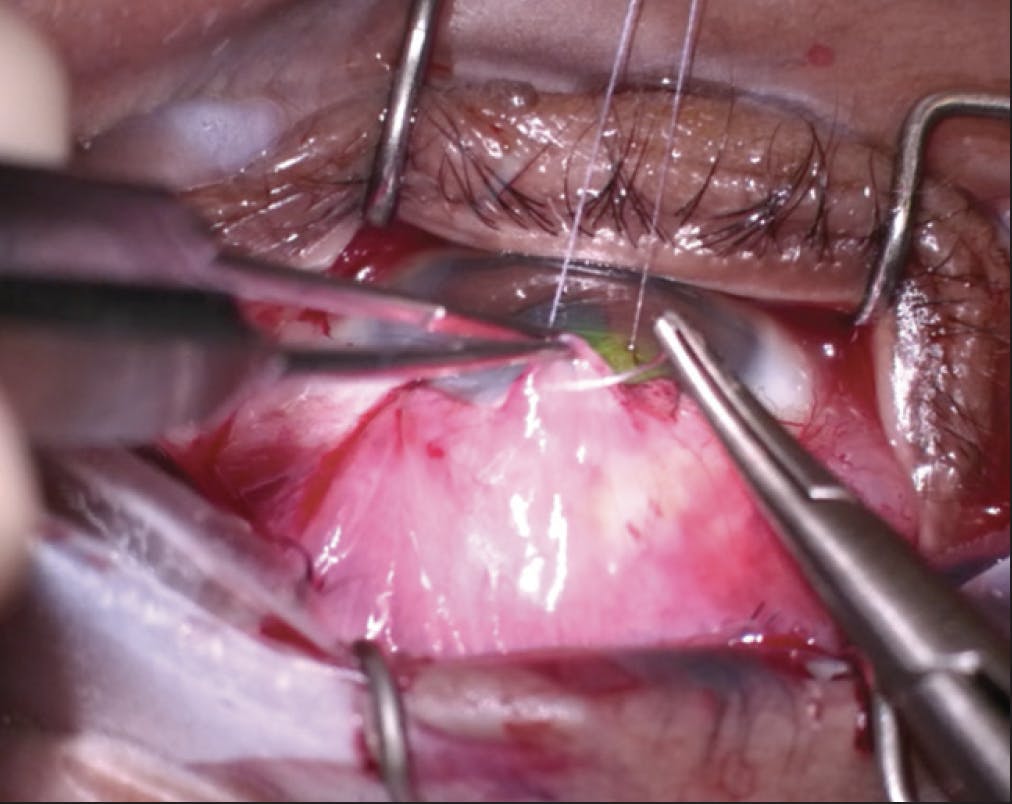

- Step No. 3: The eye was closed with a double-armed 9-0 polypropylene suture (Prolene, Ethicon) in a sandwich technique. Several bites were taken along the tip of the tongue of Tenon membrane with one end of a polypropylene needle. Each arm of the suture was then passed under the bleb, through the limbus, and into clear cornea on either side of the bleb (Figure 8). This allowed the tongue of tissue to be brought into and under the bleb. Next, the conjunctiva was advanced over the bleb, creating the second half of the sandwich. Initially, the conjunctiva was anchored to both sides of the limbus on either side of the anterior edge of the bleb with a 7-0 polyglactin suture (Vicryl, Ethicon). The polypropylene suture previously passed under the bleb was then run along the limbus to anchor the remainder of the conjunctiva (Figure 9) until the other suture end was met. The two ends were tied together (Figure 10), completing the sandwich and the bleb revision.

Figure 8. The tongue of Tenon membrane is advanced into and under the bleb space with one end of a 9-0 polypropylene suture.

Figure 9. The conjunctiva along the limbus anterior to the bleb is closed with a 9-0 polypropylene suture.